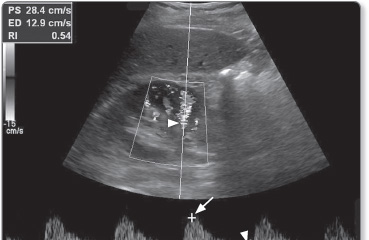

Doppler imaging

US examinations can be supplemented with Doppler scans that assess blood flow in body tissues (Figure 1.19). Doppler imaging uses the physical principle of the Doppler effect to assess whether blood is moving towards or away from the probe, and its relative velocity.

Figure 1.19: Doppler scan of the renal artery showing normal flow. The cursor for Doppler measurement has been placed on the renal artery (arrowhead). Trace shows peak systolic flow (long arrow) and end diastolic flow (short arrow) values.

By convention, blood flowing towards the probe is labelled red whereas blood flowing away from it is labelled blue on US images.